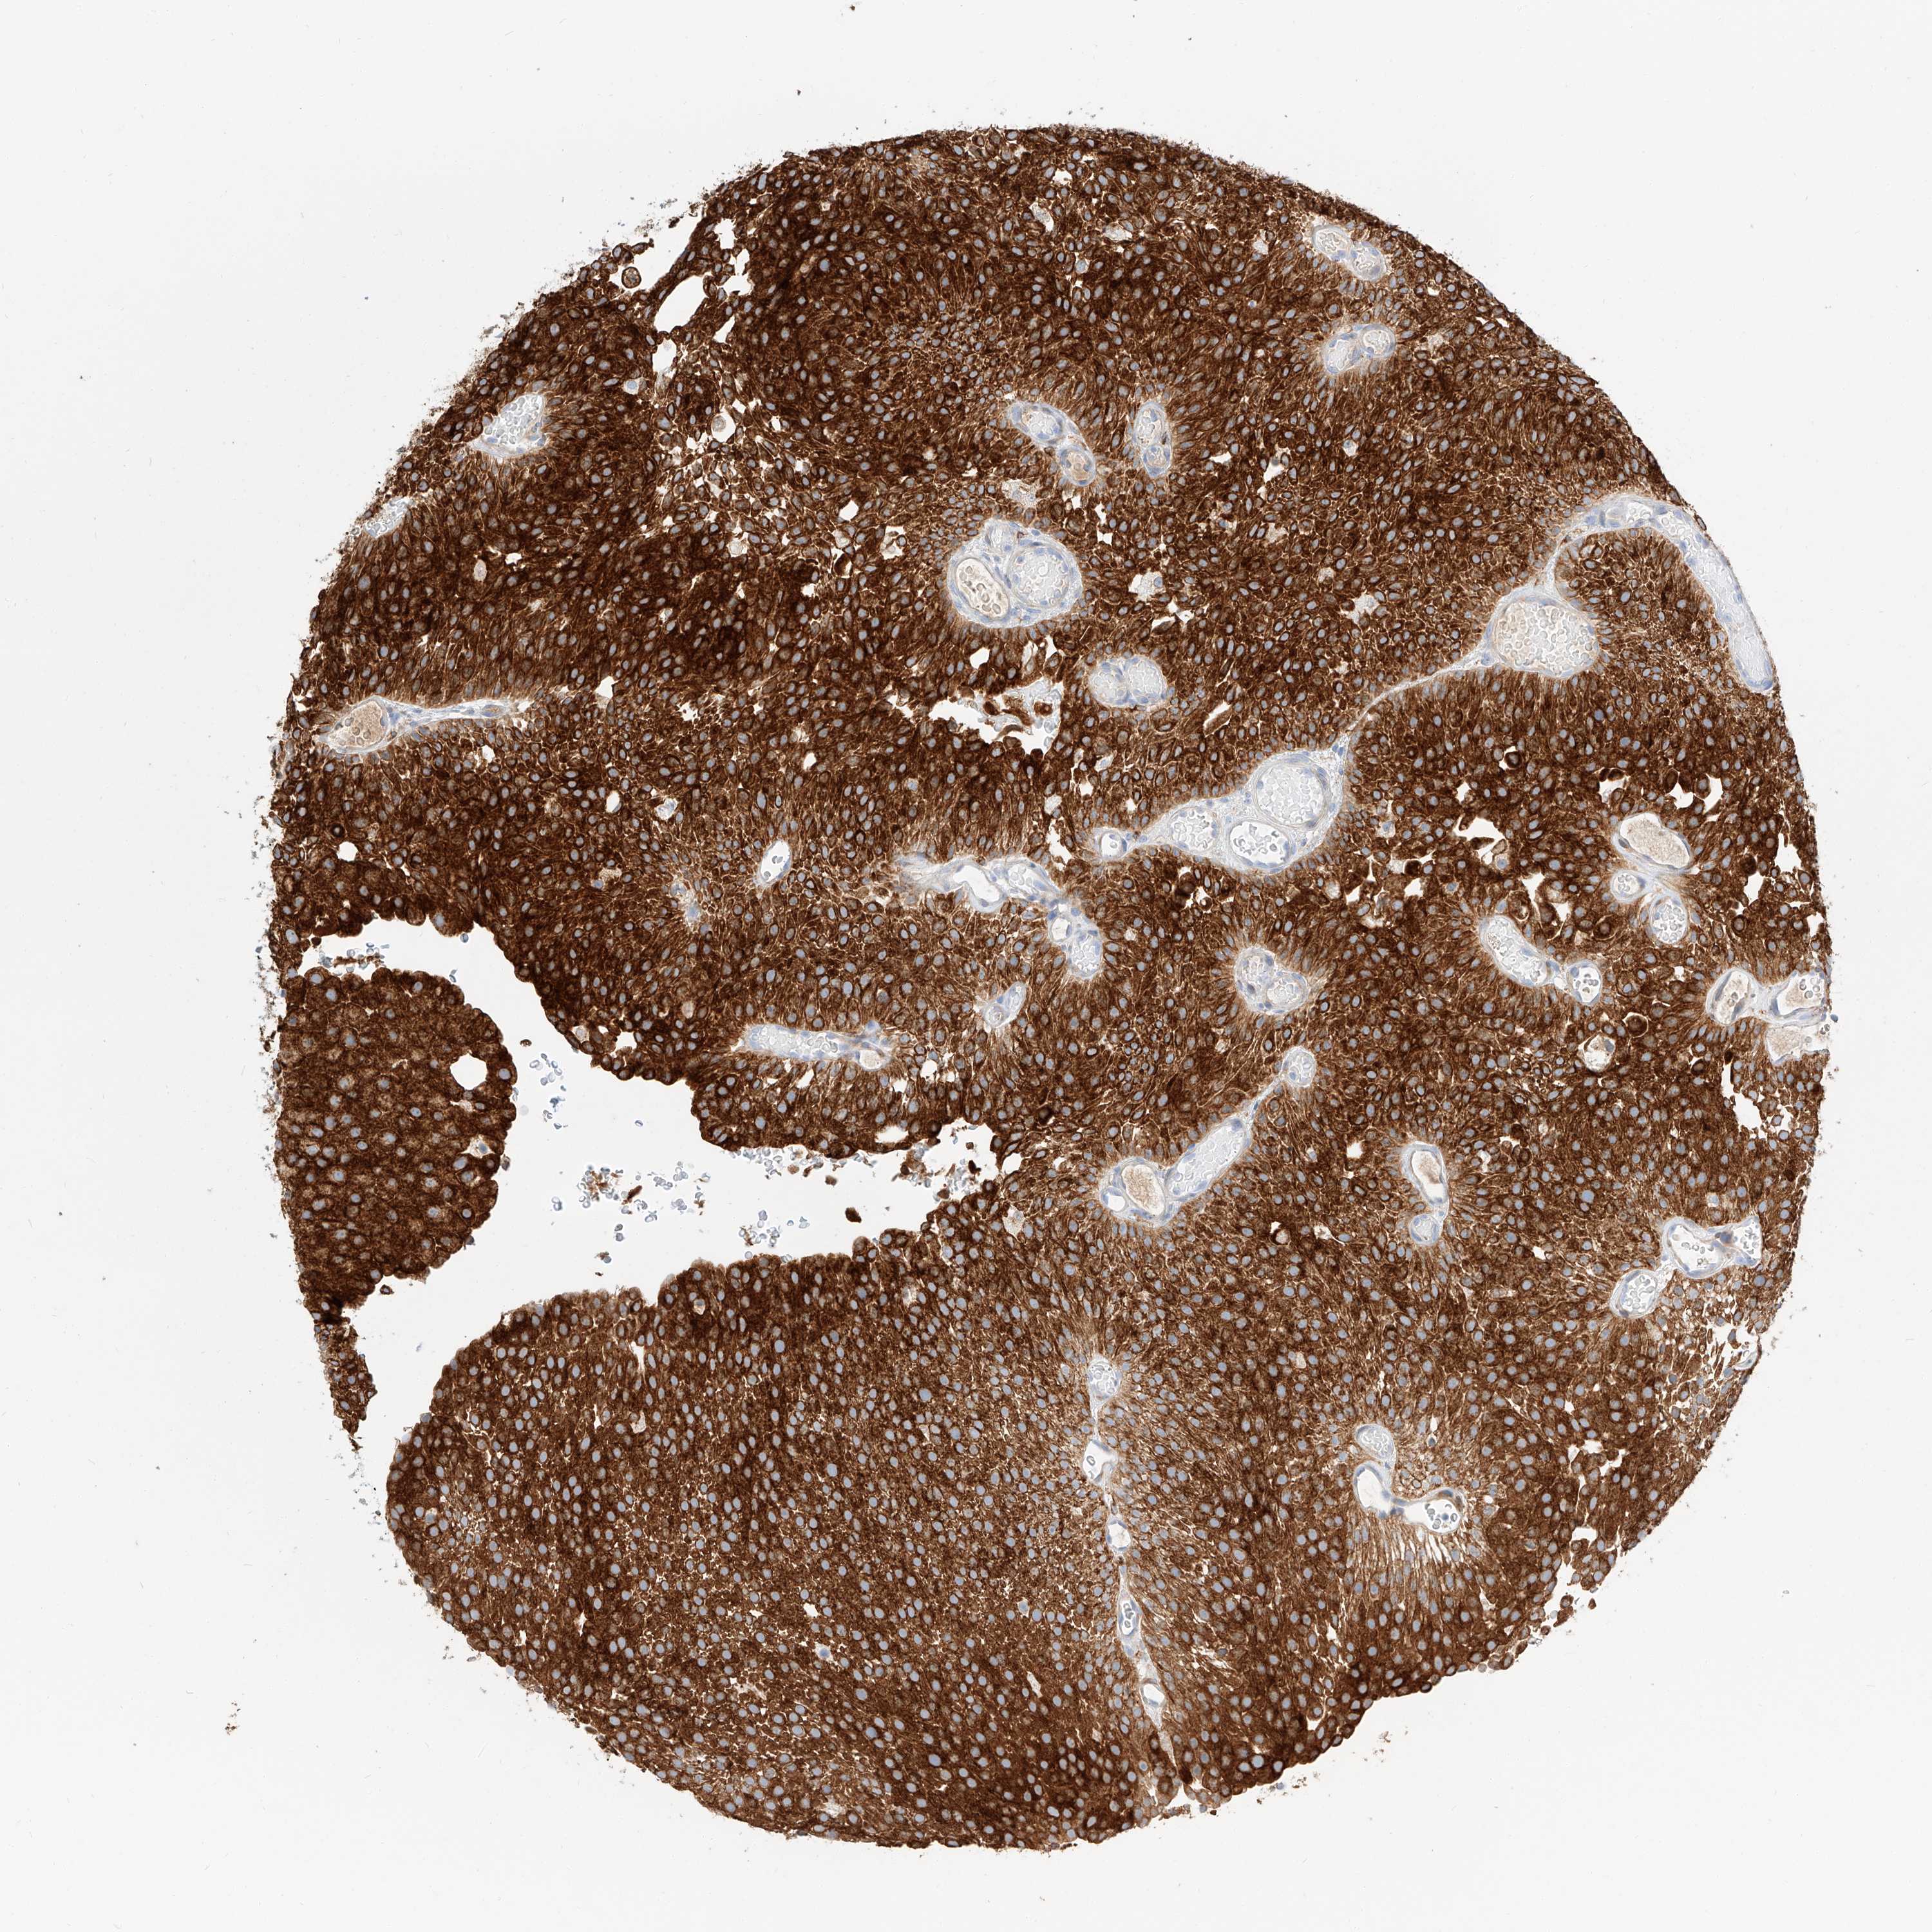

UROTHELIAL CANCER - Protein expressioni

A mouse-over function shows sample information and annotation data. Click on an image to view it in a full screen mode. Samples can be filtered based on level of antibody staining by selecting one or several of the following categories: high, medium, low and not detected. The assay and annotation is described here.

Note that samples used for immunohistochemistry by the Human Protein Atlas do not correspond to samples in the TCGA dataset.

Antibody stainingi

Antibody staining in the annotated cell types in the current human tissue is reported as not detected, low, medium, or high, based on conventional immunohistochemistry profiling in selected tissues. This score is based on the combination of the staining intensity and fraction of stained cells.

Each image is clickable and will lead to virtual microscopy that enables deeper exploration of all samples and also displays staining intensity scores, fraction scores and subcellular localization as well as patient and tissue information for each sample.

Antibody HPA029712

Antibody HPA029713

Staining

High

Medium

Low

Not detected

Intensity

Strong

Moderate

Weak

Negative

Quantity

>75%

75%-25%

<25%

None

Location

Nuclear

Cytoplasmic/membranous

Cytoplasmic/membranous,nuclear

Urothelial carcinoma, High grade